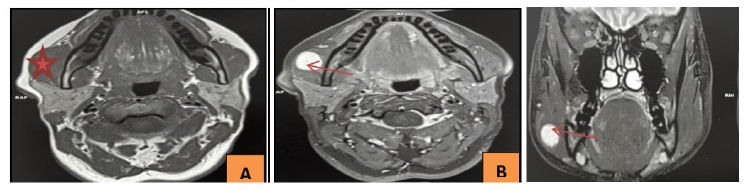

The cervico-facial MRI, performed without contrast injection in T1 and T2 sequences and reviewed by an experienced radiologist, revealed an intra-masseteric process with clear contours (15×18×13 mm) showing a hypointense signal in T1 and a hyperintense signal in T2, compatible with a benign lesion (Figure 2a, 2b, 2c).

Figure 2a: Axial slice in T1: A well-defined intramasseteric mass with hypointense signal on T1

Figure 2b: Axial slice in T2: A well-defined intramasseteric mass with hyperintense signal on T2

Figure 2c: Coronal T2 slice : an intramasseteric mass with hyperintense signal on T2

MRI is the gold standard for characterizing these lesions. T1 and T2 weighted sequences allow for the identification of the typical signal characteristics of schwannomas (hypointensity on T1 and hyperintensity on T2) [4,9]. The clinical signs, associated with a well-defined capsule, suggest a benign lesion. However, in atypical situations, additional tests such as CT scans or percutaneous biopsy may be required to rule out malignancy, especially since MRI does not reliably differentiate a schwannoma from a neurofibroma [11]. Differentiation from neurofibroma is crucial, as the latter may be associated with neurofibromatosis [7,8].